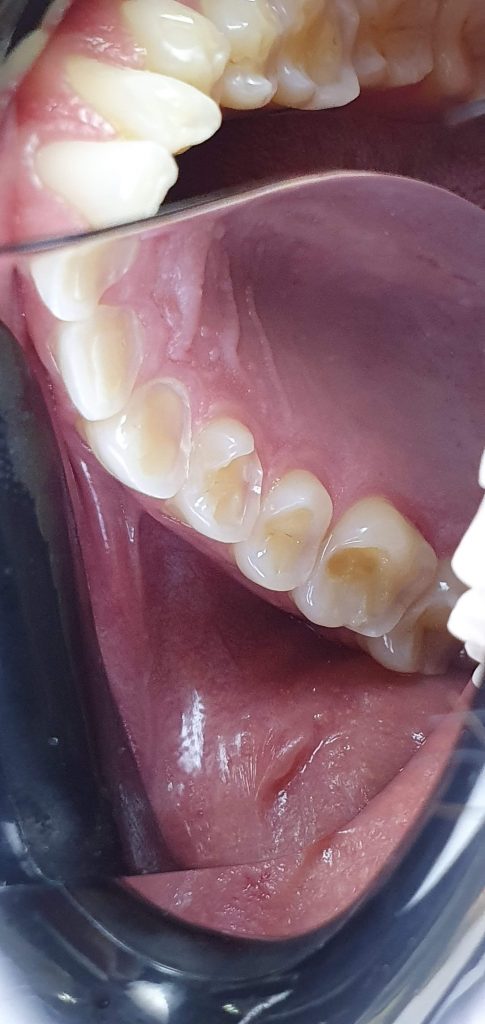

Posteriores inferiores finalizados

As Reabilitações utilizando resina composta injetável só é possível pois temos uma resina com propriedades mecânicas que a difere das resinas fluídas convencionais, a resina Clearfill A-PX Esthetics – Flow é uma resina nanohíbrida com 75% (em peso) de cargas inorgânicas e com excelente polimento sendo uma resina resistente e altamente estética. Além da escolha da resina, o planejamento reabilitador e as orientações ao paciente e uso da placa são de fundamental importância para a longevidade clínica desses casos. A adesão nos permite acrescentar e preservar o remanescente já tão desgastado. Essa opção reabilitadora tem sido a minha escolha, principalmente em pacientes tão jovens.